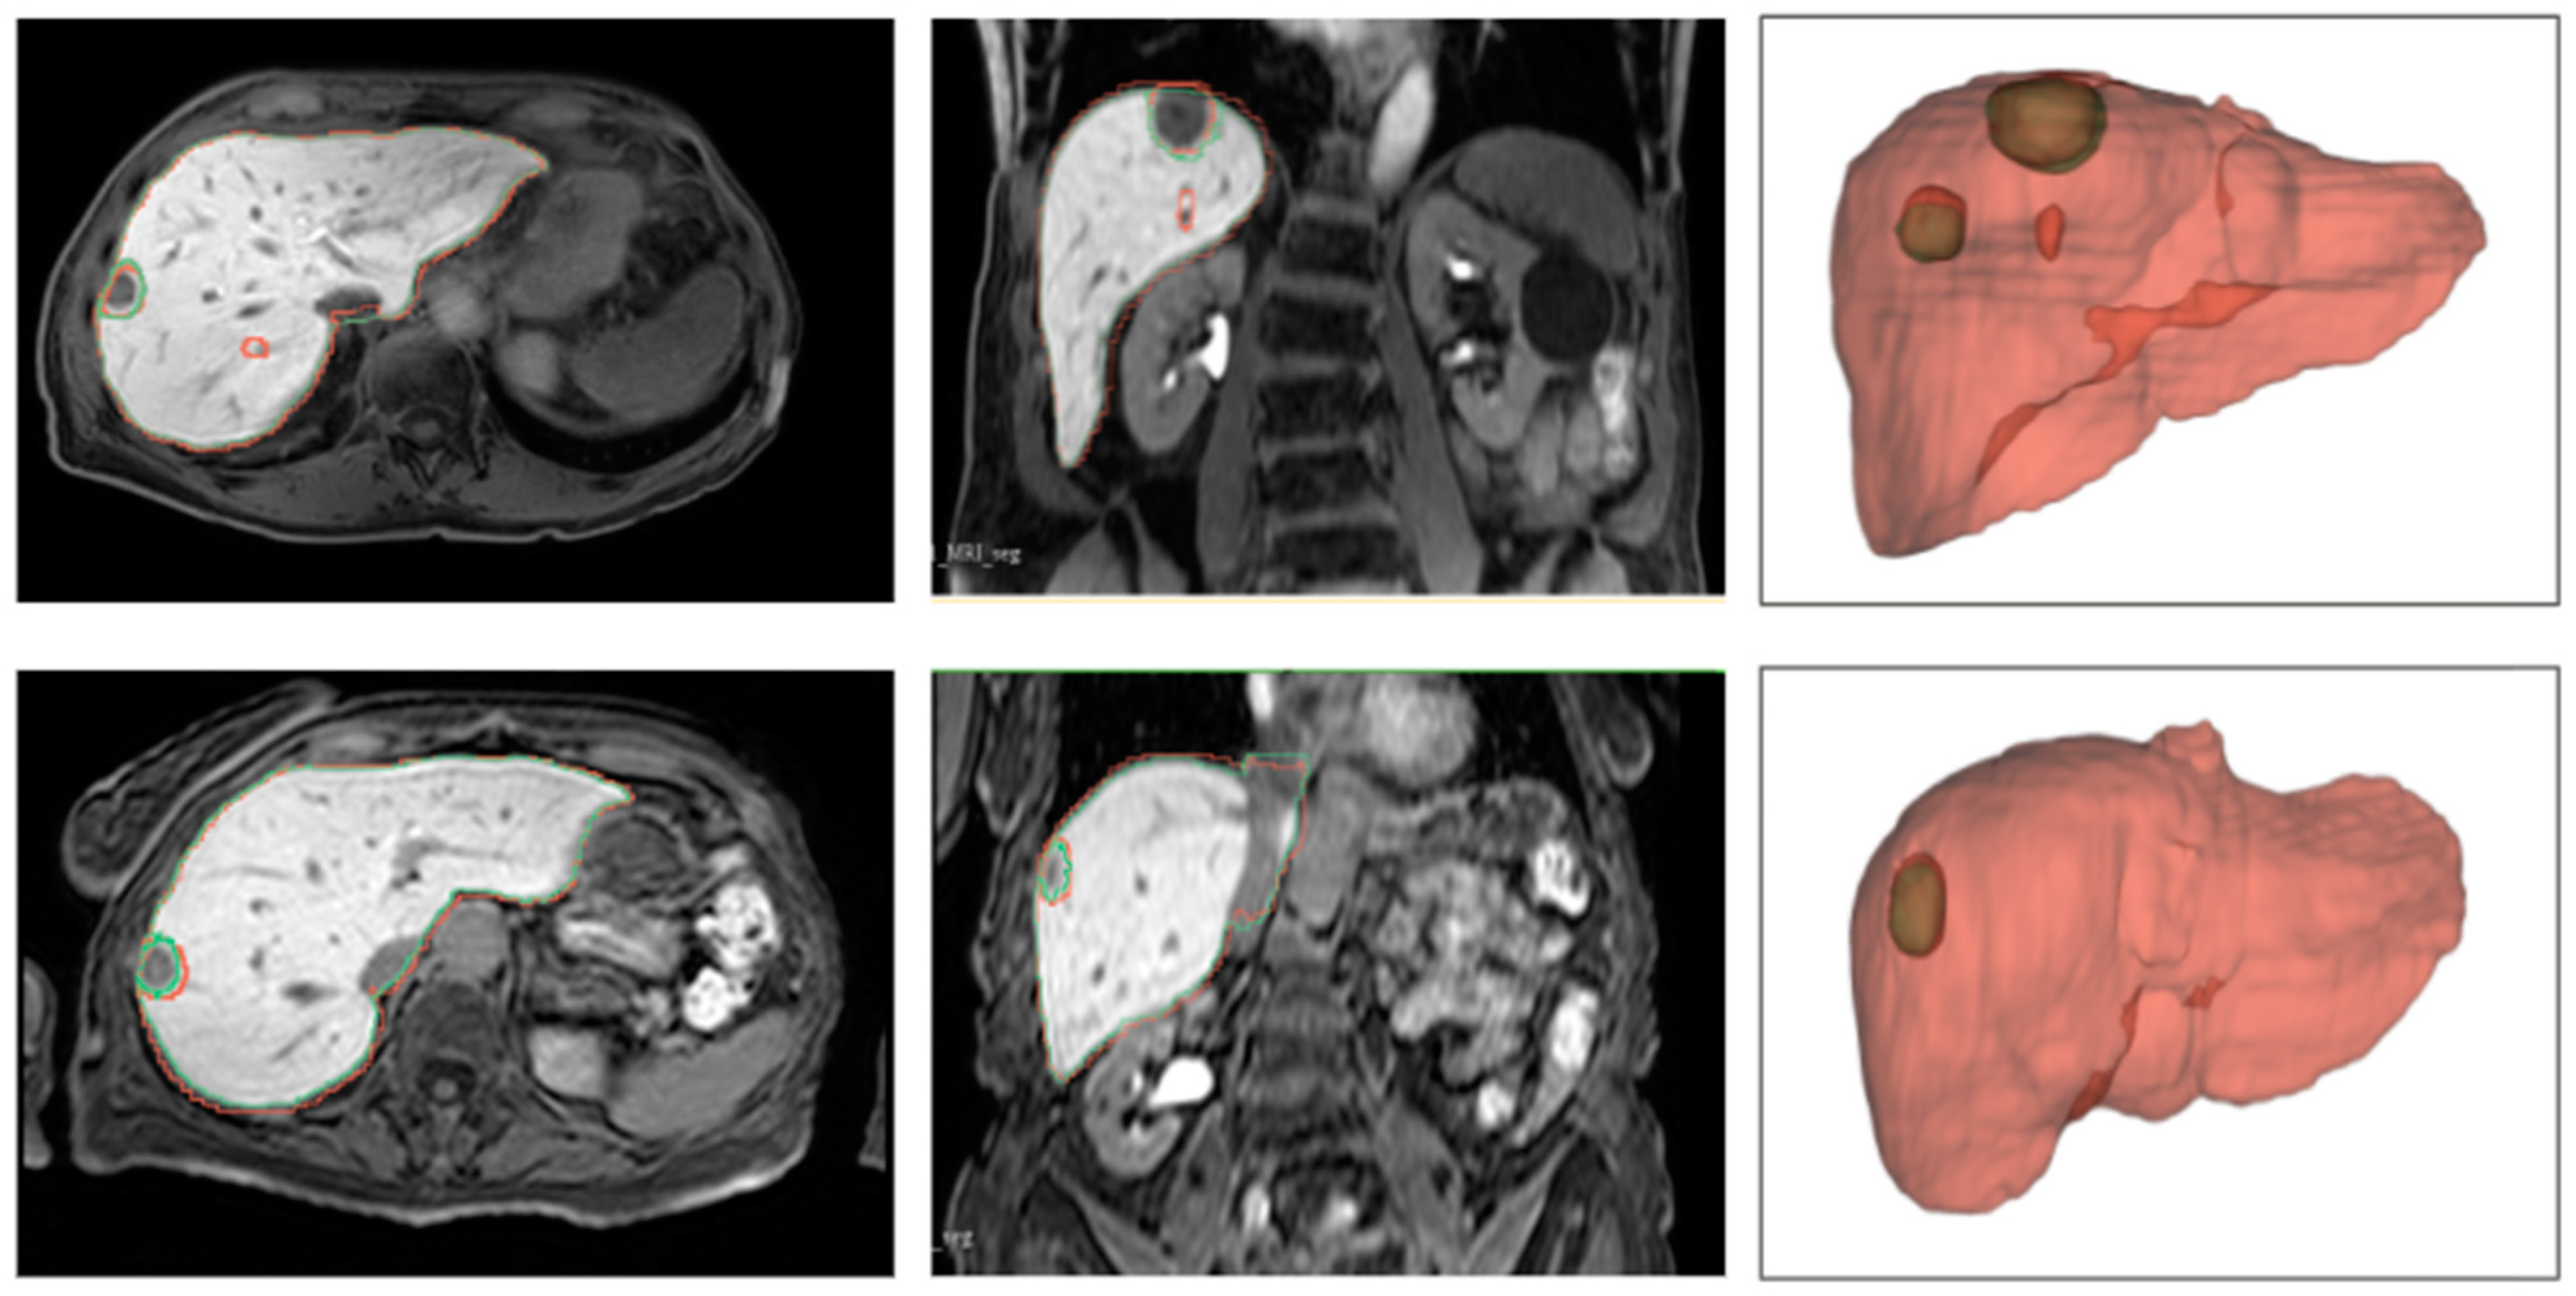

4.2.2. Qualitative Results